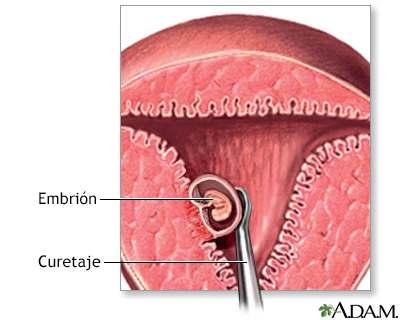

ABORTO

El aborto consiste en la interrupción del embarazo y se puede producir tanto inducir. Sea cuál sea el caso el aborto incluye con la expulsión del feto a través del anal vaginal.

ï Aborto espontáneo: Es aquel que no se da de forma intencionada sino a causa de una serie de complicaciones en el feto o a la madre. Generalmente ocurre durante las 12 primeras semanas de gestación y no precisa de ningún tipo de intervención quirúrgica pero a partir de la semana 20 pasa a denominarse muerte fetal

ï Aborto médico: Se toma un medicamento para llevar a cabo el aborto solo se puede hacer durante las nueve primeras semanas de embarazo, el más común es la mifepristona una hormona de bloquea la progesterona

ï Aborto inducido: Es aquel que se realiza por propia voluntad de la mujer.

ï Abierto quirúrgico: Se realiza una cirugía para extraer el feto.